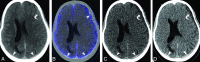

Background and purpose: Extravasation of iodinated contrast into subdural space following contrast-enhanced radiographic studies results in hyperdense subdural effusions, which can be mistaken as acute subdural hematomas on follow-up noncontrast head CTs. Our aim was to identify the factors associated with contrast-enhancing subdural effusion, characterize diffusion and washout kinetics of iodine in enhancing subdural effusion, and assess the utility of dual-energy CT in differentiating enhancing subdural effusion from subdural hematoma.

Materials and methods: We retrospectively analyzed follow-up head dual-energy CT studies in 423 patients with polytrauma who had undergone contrast-enhanced whole-body CT. Twenty-four patients with enhancing subdural effusion composed the study group, and 24 randomly selected patients with subdural hematoma were enrolled in the comparison group. Postprocessing with syngo.via was performed to determine the diffusion and washout kinetics of iodine. The sensitivity and specificity of dual-energy CT for the diagnosis of enhancing subdural effusion were determined with 120-kV, virtual monochromatic energy (190-keV) and virtual noncontrast images.

Results: Patients with enhancing subdural effusion were significantly older (mean, 69 years; 95% CI, 60-78 years; P < .001) and had a higher incidence of intracranial hemorrhage (P = .001). Peak iodine concentration in enhancing subdural effusions was reached within the first 8 hours of contrast administration with a mean of 0.98 mg/mL (95% CI, 0.81-1.13 mg/mL), and complete washout was achieved at 38 hours. For the presence of a hyperdense subdural collection on 120-kV images with a loss of hyperattenuation on 190-keV and virtual noncontrast images, when considered as a true-positive for enhancing subdural effusion, the sensitivity was 100% (95% CI, 85.75%-100%) and the specificity was 91.67% (95% CI, 73%-99%).

Conclusions: Dual-energy CT has a high sensitivity and specificity in differentiating enhancing subdural effusion from subdural hematoma. Hence, dual-energy CT has a potential to obviate follow-up studies.